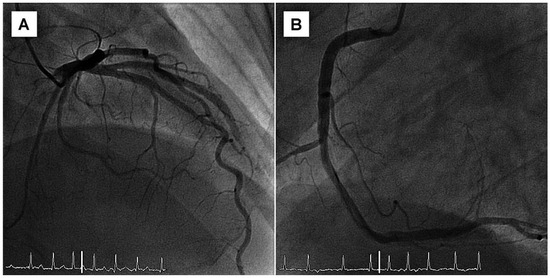

Giant Apical Aneurysm without Coronary Artery Disease

by Stéphane Chevallier and Jean-Christophe Stauffer

Abstract

A 66-year-old patient with some years’ history of apical hypertrophic cardiomyopathy treated by beta-blockers attended for follow-up echocardiography [...] Full article

The differential diagnosis of recurrent chest pain is manifold. Although it is unlikely in younger people, a cardiac origin should always be considered. We report a case of recurrent chest pain which was initially considered to have a gastrointestinal or psychic origin. A [...] Read more.

The differential diagnosis of recurrent chest pain is manifold. Although it is unlikely in younger people, a cardiac origin should always be considered. We report a case of recurrent chest pain which was initially considered to have a gastrointestinal or psychic origin. A circadian pattern of the pain was conspicuous. Finally, coronary angiography performed in the setting of an acute coronary syndrome followed by life-threatening rhythm disturbances established the diagnosis. Full article

Show Figures

Figure 1